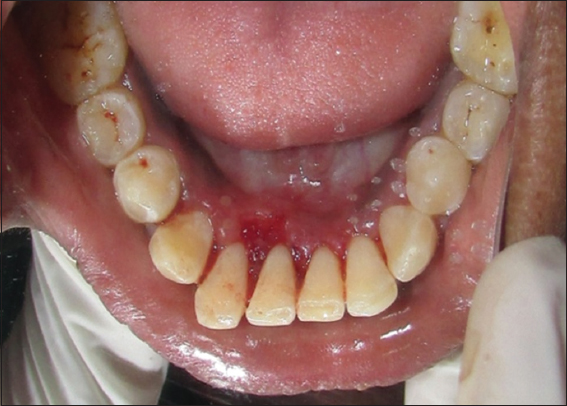

On the basis of history and clinical findings, a provisional diagnosis of irritation fibroma was given. The list of differential diagnosis included chronic fibrous epulis, peripheral giant cell granuloma, osteosarcoma, chondrosarcoma, pyogenic granuloma, and peripheral odontogenic fibroma. The investigations included complete hemogram, intraoral radiographs, and excisional biopsy of the lesion. Routine hematological investigation values were also found to be within normal limits. No radiographical changes related to the bone were seen [Figure 2]. As the patient reported discomfort during eating and while speaking, it was decided to go for an excisional biopsy performed under local anesthesia using a scalpel [Figure 3]. The excised tissue [Figure 4] was sent to the department of oral pathology for histopathological examination and H and E stained section revealed parakeratinized stratified squamous epithelium with elongated rete ridges. Irregular multiple foci of homogenous calcified areas were evident within the connective tissue. Thus, a final diagnosis of irritation fibroma was given [Figure 5]. Patient was recalled after 1 week for revaluation which shows satisfactorily healing and patient was asked to maintain oral hygiene [Figure 6]. No recurrence of fibroma was seen when patient was recalled after 6 months for follow-up [Figure 7].

Figure 3: Immediate post-operative